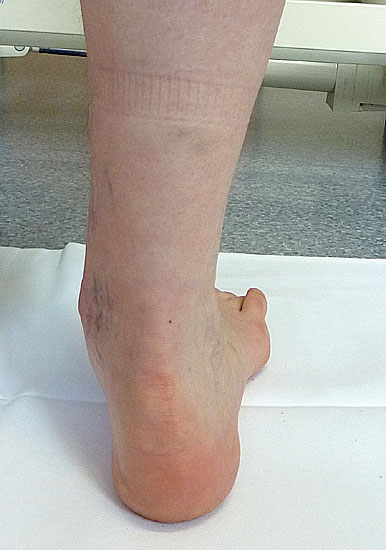

• Morphologie der Beinmuskeln (Seitendifferenz, Waden distal dünn (Abb. 11), Narben)

Inspektion im Liegen von plantar

• Beschwielung

• plantare Prominenzen